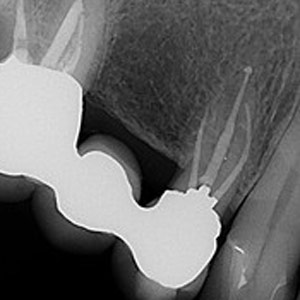

NON-SURGICAL

Oftentimes, our patients need non-surgical treatments that require minimal intervention. This intertwines with our belief that preventative maintenance and regular dental care can minimize the need for surgeries. You can rest assured that our highly trained and experienced team consistently provides the highest quality endodontic treatments and assistance available in the North Shore.